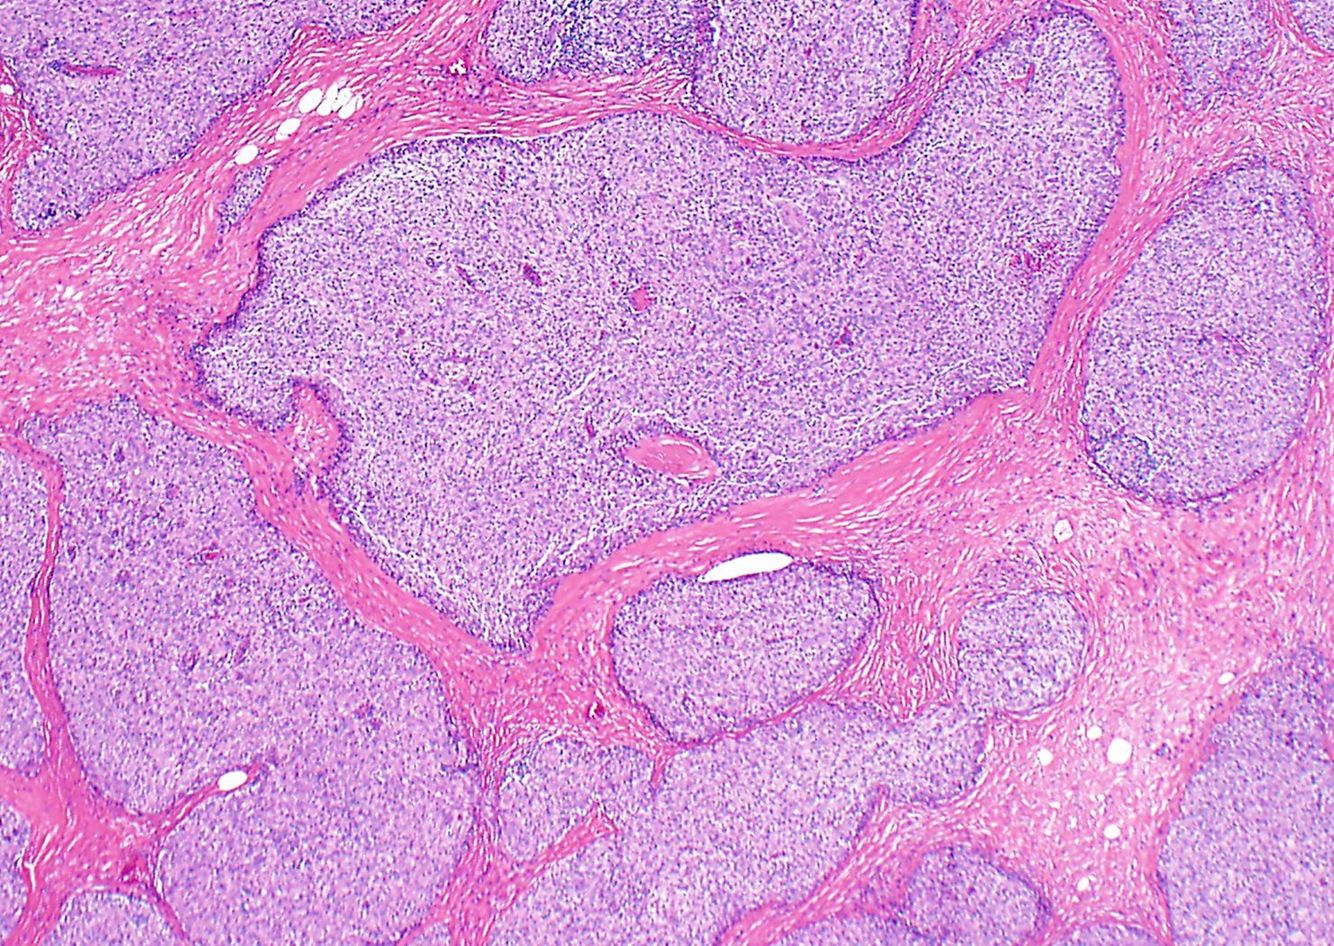

Thymoma, type B2

Type B2 thymomas are characterized by a mixed epithelial cell and lymphocyte picture.

Instead of a straight up sea of lymphocytes, these tumors have a smattering of lymphocytes and large stromal cells with prominent nucleoli. They may have some medullary island, but will not have fully differentiated Hassall corpuscles.